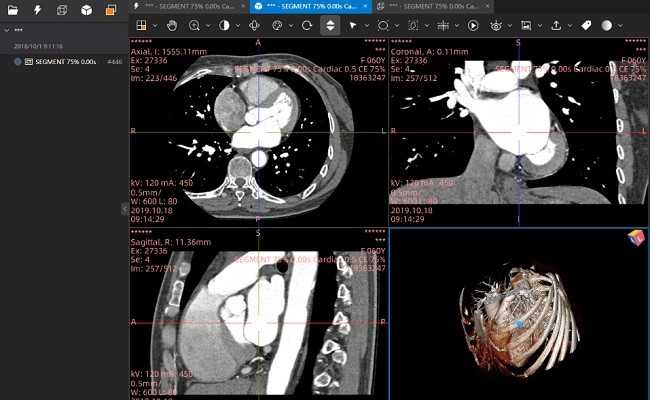

医学影像,用小赛看看。小赛看看DICOM Viewer是一款免费的医学影像DICOM浏览器。支持PET-CT图像融合,MPR浏览,SUV测量,DICOM文件匿名化,DICOM Tag查看等功能。

提供丰富的图像浏览功能,包括MPR、3D浏览、电影播放、伪彩、ROI测量、 HU值和SUV值测量、匿名化等

专业的核医学图像融合功能,支持SPECT/CT、PET/CT、PET/MR融合

支持DICOM影像的MPR重建

支持PET-CT影像的融合显示